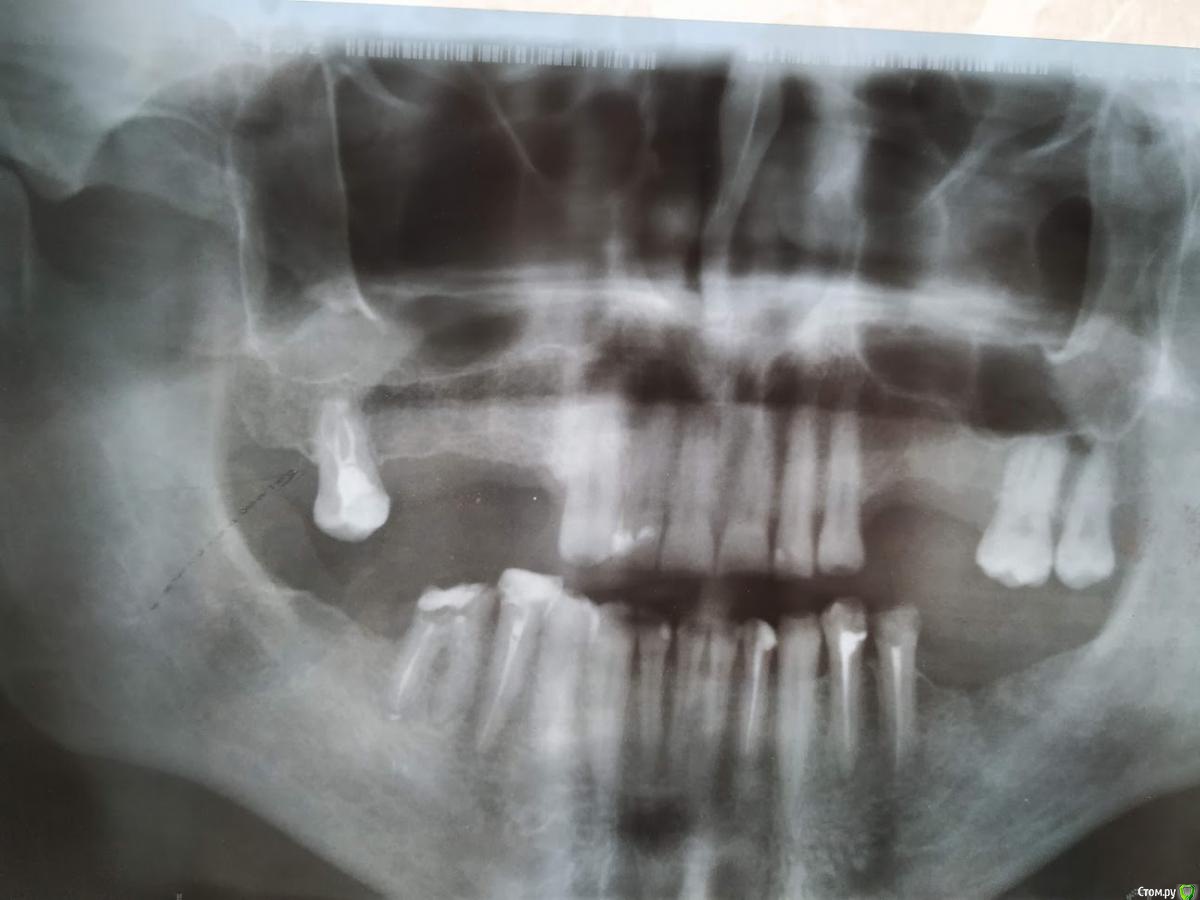

Валдемар Опубликовано 29 августа, 2019 Поделиться Опубликовано 29 августа, 2019 Добрый день,Уже был здесь, но прошлые явки и пароли забыл.12.04 операция 4 импланта20.04 вылез первый15.05 вылез второй26.08 удален 3ий28.08 удален 4ыйПотрачено 100тр, время и нервы. Возвращено 7200 за 2 импланта, за 2 которые удаляли деньги не вернули, так как не было показаний. А то что голова болит, переносица, лоб - ет не от этого. Удалил и всё прошло, кстати.Вопрос:1). Справа десны (кости) реально меньше чет слева. Что с этим делать. Как сделать чтобы кости хоть немного прибавилось? Без имплантации, просто кость с десной нарастить.2) 100% неприживаемости - ето как? Диабет, спид, гепатит по диспансаризации сдавал - отрицательно. Какие мои действия теперь? по новой имплантироваться и если опять не приживется, опять по новой? Ссылка на комментарий

Валдемар Опубликовано 31 августа, 2019 Автор Поделиться Опубликовано 31 августа, 2019 Я снимок после удаления не делал, но у меня реально справа десна тоньще раза в два. Там воспаление месяца два шло. В имплантацию больше не верю, вернее, боюсь. Боюсь нового стресса для организма. Верил в современную медицину, российскую, смотрел на людей с коленками кривыми, тазобедренными суставами проблемными, говорил че вы ждете, щас раз и коленку и тазобед сустав меняют и как новенький, а теперь понимаю, фиг там. Китайское что рибудь поставят, или руки у дохтора не оттудава, и всё, можно на костылях оставшуюся жизнь бегать...Потому люди до последнего и тянут. Ссылка на комментарий